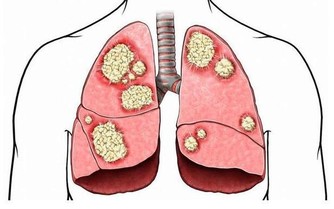

3.骨質密度

人的骨質密度和營養、發育、遺傳等因素影響,一般從35歲開始,骨質密度開始下降,尤其女人在絕經後5年內,骨量缺失最快。

除了藉由骨質密度檢測了解之外,平時應該不挑食,藉由吃豆腐、蝦皮、喝牛奶等方式攝取鈣和維生素D,同時要運動、曬太陽,預防比治療,食補勝過藥物,更有效果。